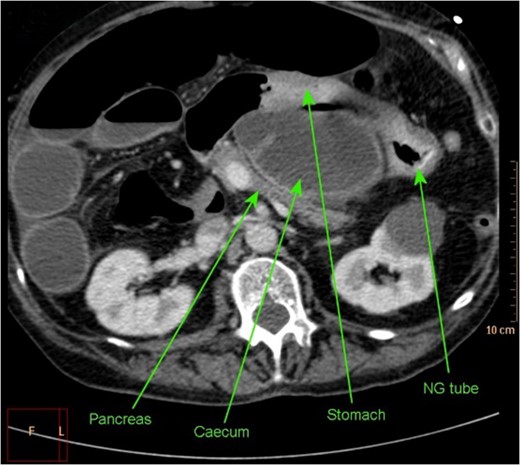

Axial section of CT abdomen demonstrating NG tube in stomach, with successful decompression of obstructed gastric outlet, however obstructed caecum clearly visible within lesser sac.